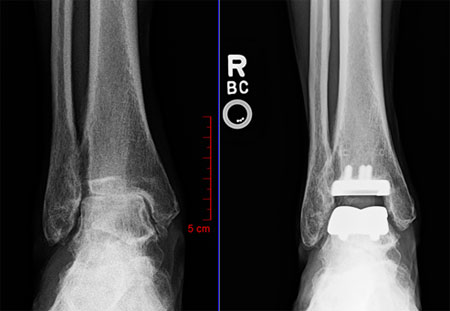

During total ankle replacement surgery, a surgeon removes some bony tissue from the end of the lower leg bone (tibia) and the top of the upper foot bone (talus). The surgeon then tamps metal implants into position. The implants are separated by a plastic spacer (see before and after images below).

Dr. Matthew Buchanan replaced my right ankle in early 2020. Because the surgery replaced only the parts of my ankle (see picture of X-ray) that were rubbing each other, soft tissue was minimally affected and thus pain free. I was back at work in a walking boot, aided by a knee scooter, in three weeks. The swelling was very minimal if any. Dr. Buchanan monitored my progress every week. The walking boot came off five weeks after surgery, and the longest-lasting adjustment for me was to consciously resume a normal gait because even with no pain, I basically had to retrain my right leg to take a full stride and my left leg not to compensate. I never imagined that I would be walking normally, and eventually, working out, with no pain.